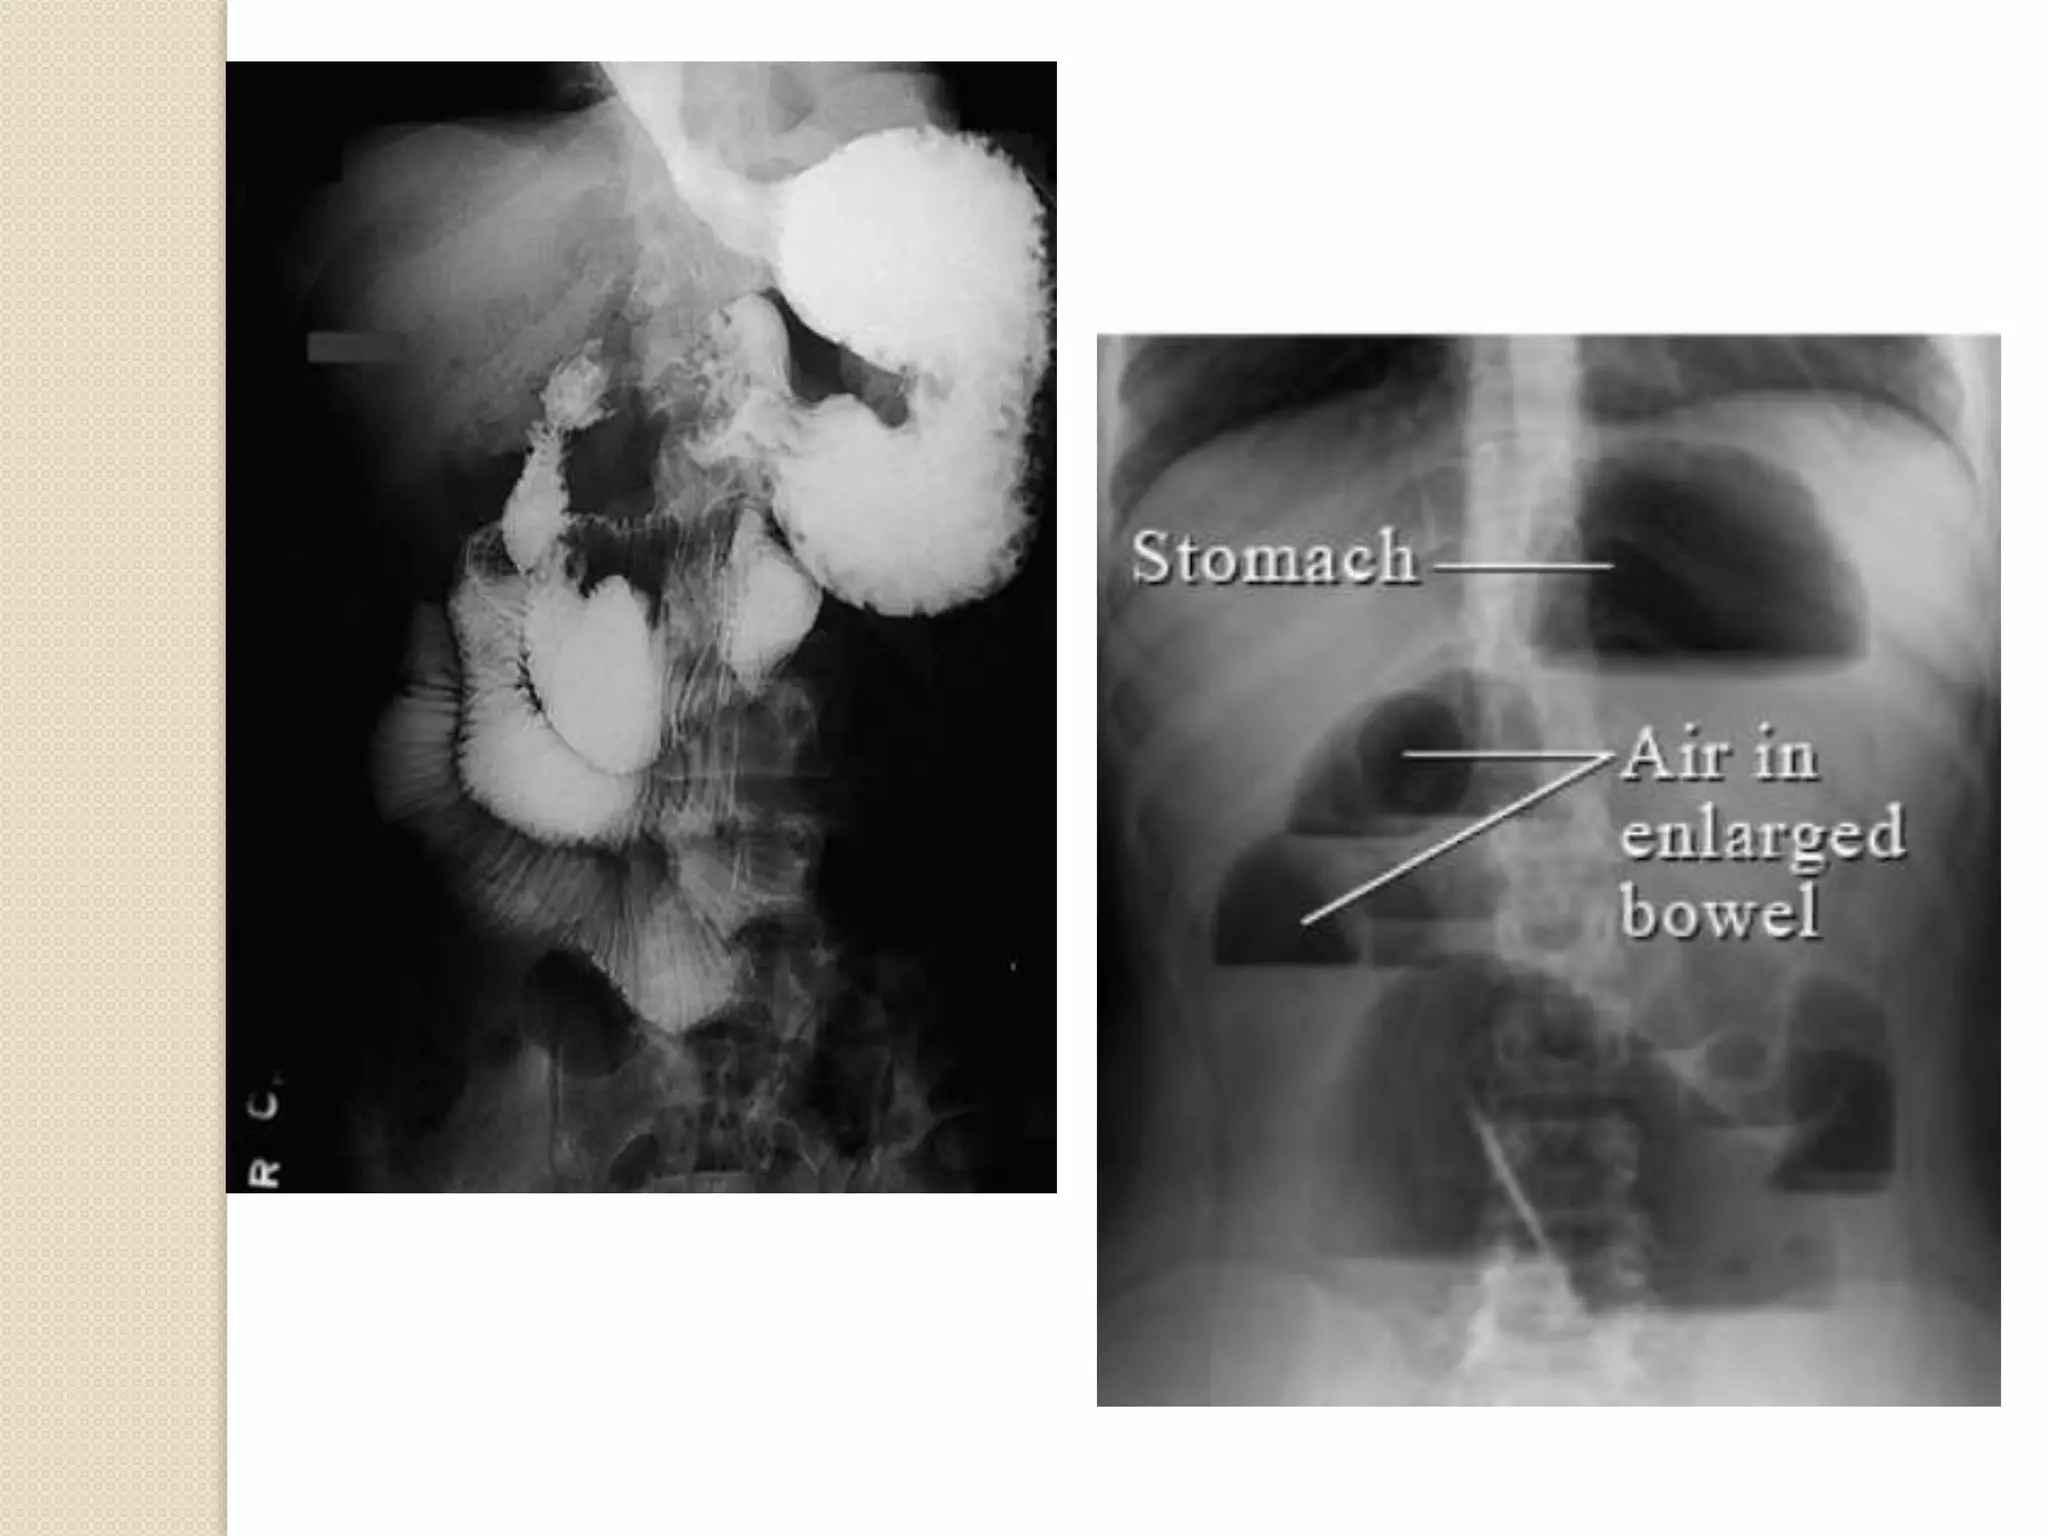

Intestinal involvement

1. Esophagus: hypomotility and retrosternal pain,

reflux esophagitis, stricture

2. Stomach: delayed emptying

3. Small intestine: pseudo-obstruction, paralytic ileus,

malabsorption

4. Large intestine: chronic constipation and fecal

impaction diverticula

Gastrointestinal

 Disordered peristalsis of the lower two thirds of the

esophagus presents as dysphagia

 Impaired function of the lower esophageal sphincter

 Chronic esophageal reflux include erosive esophagitis

with bleeding, Barrett's esophagus, and lower

esophageal stricture

 Involvement of the stomach occurs in systemic sclerosis

and presents clinically as ease of satiety and on

occasion as either functional gastric outlet

obstruction or acute gastric dilatation.

Small bowel involvement

 Intermittent bloating with abdominal cramps,

intermittent or chronic diarrhea, and presentations

suggestive of intestinal obstruction.

 Malabsorption occurs

 Bacterial overgrowth in areas of intestinal stasis

occurs frequently

Colonic involvement

 Is present in the majority of patients with systemic

sclerosis

 Is infrequently a prominent cause of clinical

symptoms

 Constipation, obstipation, and Pseudo-obstruction

may occur and are related to abnormal colonic

motility